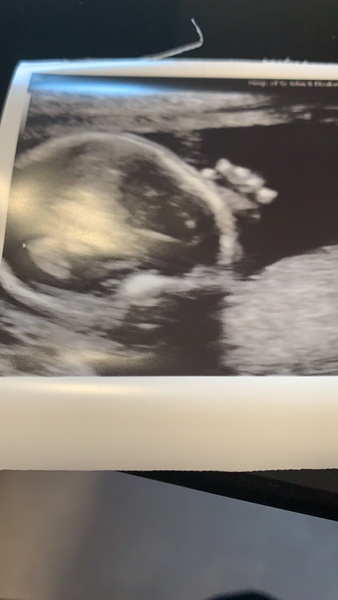

I am so relieved! Wonder whether scanxiety will ever subside! A little wave from my baby boy to you ladies - you can see his fingers so clearly!

Hello!! Saw baby boy again today ❤️💙 we interrupted his nap today lol. He did a few waves but was all curled up clearly wanting us to stop bothering him 😂 but still measuring a week ahead 👍🏻 all measurements good, actually put me an extra day ahead 🙈 said she works for nhs hospital as well as this job and does Papp-a growth scans and has never seen any growth issues just down to that! Showed me the placenta and the cord pulsating. She was so lovely. So good to know all is ok.